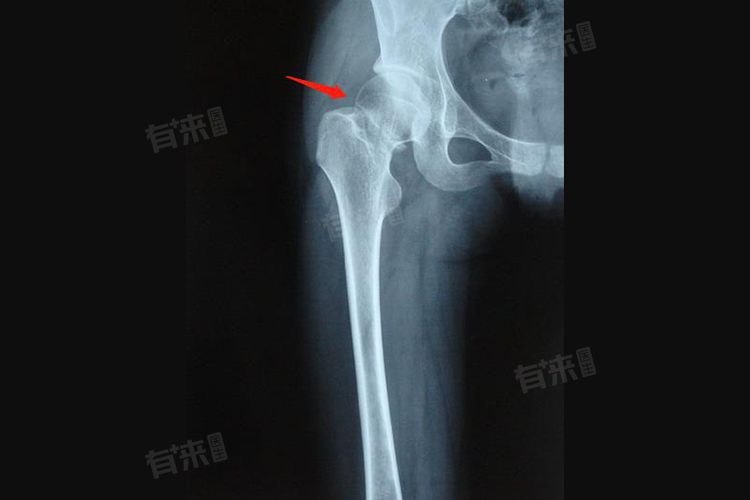

股骨颈手术后有诸多禁忌,并非固定的三个禁忌,主要包括避免过早负重、忽视伤口护理以及不良生活习惯。因个体恢复情况有别,术后护理需结合自身状况。

1、忌过早负重:术后骨骼愈合需要时间,过早负重易使刚固定的股骨颈移位,影响愈合效果,甚至可能导致内固定物松动、断裂。通常在术后初期,需严格遵循医嘱使用辅助器械,如拐杖,逐步增加负重,不可急于求成自行过早负重行走。